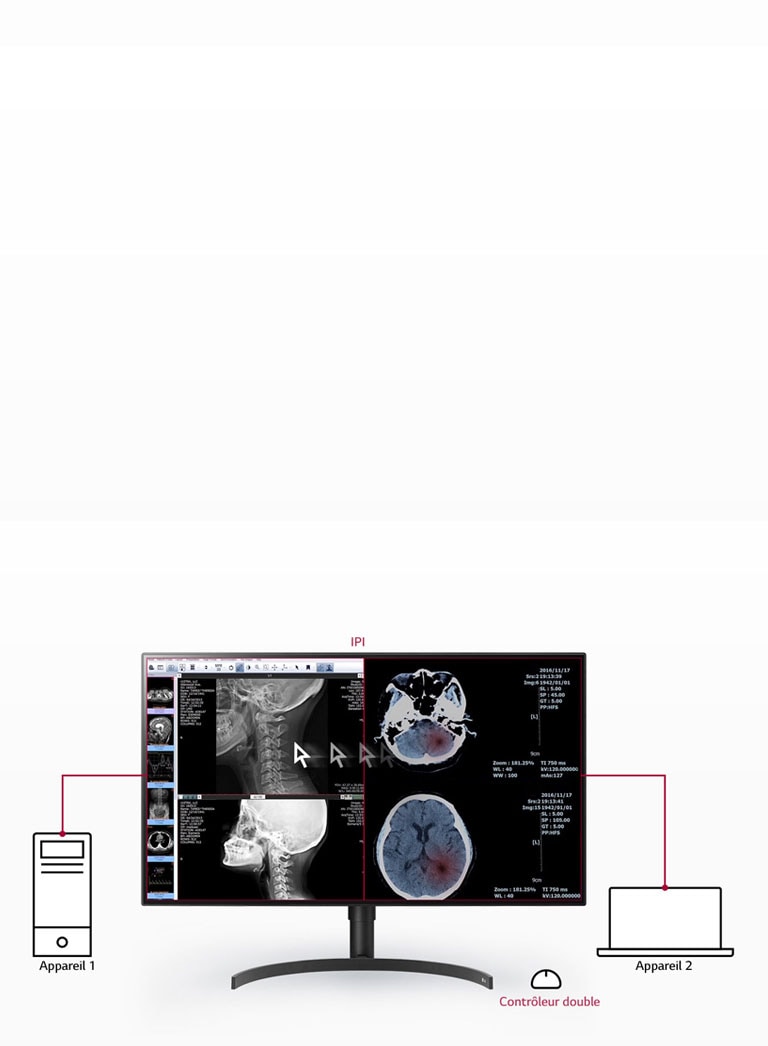

- IPI / Contrôleur double

Contrôleur double

OUI

PBP (image par image)

2 PBP